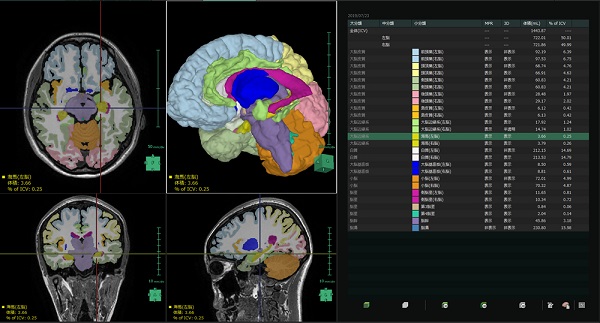

(3)脳区域解析機能

MRI 画像から解剖学的に一意に決まっている区域(15 区域)を自動で抽出し、体積の定量化などを行うことが可能である。

将来は臨床現場の意見を取り入れ、アルツハイマーなど脳が萎縮する脳疾患の治療への応用を検討していく。